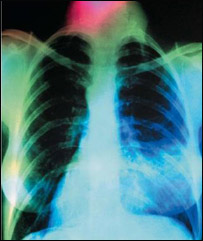

سينه بغل

سينه بغل يا نمونيا به التهاب شديد ريه ها يا شش ها گفته می شود.

البته از اثر اين بيماری، شش ها پر از چرک شده و رسيدن اکسيجن به خون با مشکل مواجه می شود.

درين بيماری بدن به کاهش اکسيجن دچار شده، ريه ها مملو از چرک و آب زرد رنگ می شوند .

شش ها کار اصلی خود را که اخذ اکسيجن است به درستی انجام داده نمی تواند و بدن به کاهش اکسيجن دچار می شود.